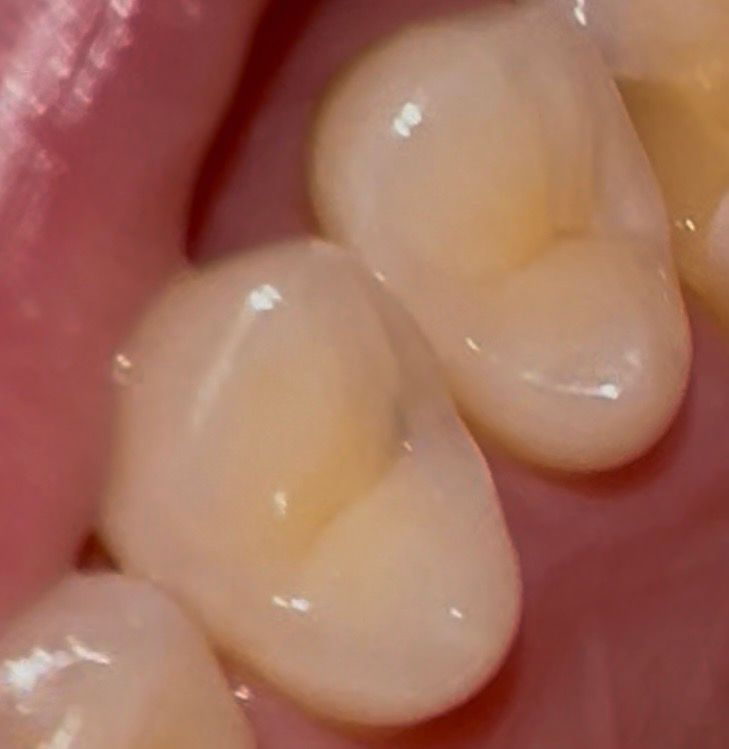

• 2번 째 사진

사진으로는 치아인접면에 색이 변한 부분이 보입니다. 하지만 X레이 사진으로는 충치가 커 보이진 않습니다. 따라서 치실 등으로 해당 부위를 관리해 보는 것이 좋을 것으로 생각되며 주기적으로 치과에서 검진을 받아 충치가 커지고 있지 않은지 확인하는 것이 좋을 것으로 생각됩니다.

1. 육안으로 봤을 때 충치가 보이는 상태 맞고, 안쪽으로 꽤 깊을 수도 있습니다. 방사선 사진에선 보이지 않는데요